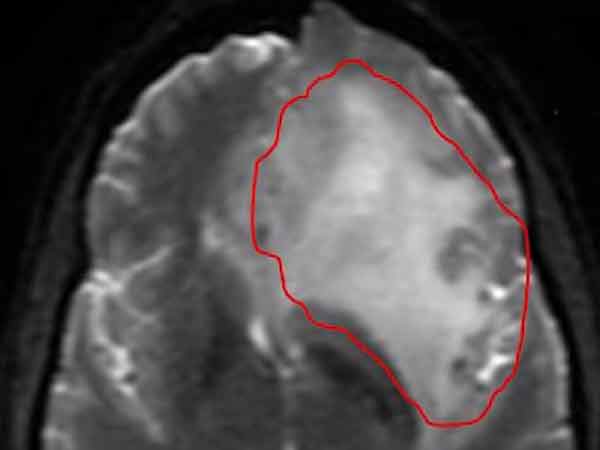

அமெரிக்காவின் ஒரேகான் மாகாணத்தை சேர்ந்த 29 வயது பிரிட்னி மேனார்ட், கடந்த ஆண்டு டேனை திருமணம் செய்தபோது, எல்லா பெண்களையும்போல, தானும் பல ஆண்டுகள் கணவனோடு மகிழ்ச்சியாக வாழ்ந்து, பல குழந்தைகளை பெறுவோம் என்றுதான் நினைத்திருந்தார். ஆனால் கடந்த ஜனவரியில், தலைவலிக்காக எம்ஆர்ஐ ஸ்கேன் செய்து பார்த்தபோது மூளையில் கட்டி வளர்ந்திருப்பதாக டாக்டர் சொன்னபோது அவரது கனவுகள் ஒரே நிமிடத்தில் பொசுங்கி போகின.

தாங்க முடியாத தலைவலியால் மீண்டும் மருத்துவமனையில் சோதித்து பார்த்தபோது, டாக்டர்களே எதிர்பார்க்காத வகையில் கட்டி உயிர்கொல்லி கேன்சராக மாறி பிரிட்னியின் உயிரை விழுங்கி கொண்டிருந்தது தெரியவந்தது. 10 ஆண்டுகளாவது வாழ்வோம் என்ற அற்ப சந்தோஷத்திலும் மண்ணைப்போட்ட நோய், பிரிட்னி இன்றும் 14 மாதங்கள்தான் உயிரோடு இருப்பார் என்று டாக்டர்களை சொல்லச் சொல்லியது.